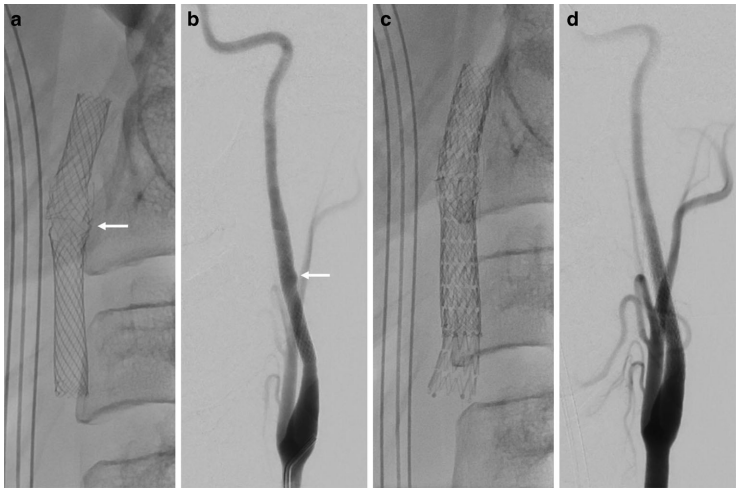

患者首次就诊时表现为急性左半球卒中症状,包括失语、偏瘫和凝视偏差。CTA显示左ICA不规则管腔提示夹层形成,CT灌注证实左中央区血流灌注异常。DSA进一步验证夹层存在,急诊植入Carotid Wallstent支架(7x30mm)并行机械取栓后,血管再通成功(TICI 3级)。术后6个月随访未见异常,但12个月后因症状复发再次入院,CTA发现支架中段断裂伴MCA-M3段闭塞,同时发现断裂处与过长茎突(>2.5cm)紧密相邻。无增强CT显示多处支架碎片迁移至左额叶及顶枕裂区域,这些碎片在首次治疗后的影像中并未出现。

患者接受系统性溶栓及机械取栓后,因既往出血并发症暂未立即再植入支架。确诊鹰综合征后,行择期经口茎突切除术,内镜辅助下于颅底离断茎突并打磨骨性突起。术后6周再植入闭孔设计支架(CGuard, 8x40mm),术后血管轮廓恢复平滑。术后6个月随访患者仍遗留轻度神经功能缺损。